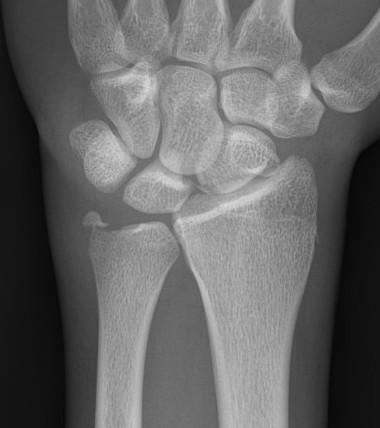

Galeazzi fracture

Galeazzi fracture with DRUJ disruption

Incidence of DRUJ instability after radius ORIF

Rettig et al J Hand Surg Am 2001

- 40 patients with Galeazzi fracture dislocations

- DRUJ instability after radius ORIF

- Type 1: radius fracture < 7.5 cm to articular surface: 55% DRUJ instability

- TYpe II: radius fracture > 7.5 cm to articular surface: 6% DRUJ instability